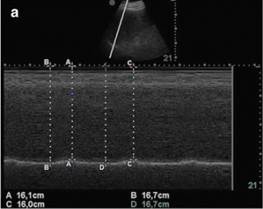

La ecografía diafragmática se realiza utilizando una sonda de matriz en fase de 3,5 a 5 MHz. La sonda se coloca inmediatamente debajo del margen costal derecho o izquierdo en la línea clavicular media, o en la línea axilar anterior derecha o izquierda y se dirige medial, cefálica y dorsalmente, de modo que el haz de ultrasonido alcance perpendicularmente el tercio posterior del correspondiente hemi-diafragma (Fig.1a). El modo bidimensional (2D) se utiliza inicialmente para obtener el mejor abordaje y seleccionar la línea de exploración; el modo M se usa entonces para visualizar el movimiento de las estructuras anatómicas a lo largo de la línea seleccionada (Fig.  1b). El movimiento diafragmático inspiratorio normal es caudal, ya que el diafragma se mueve hacia la sonda; el movimiento espiratorio normal es craneal, como los movimientos de diafragma de distancia desde la sonda (Fig.  1c) (19) (20)

GRÁFICO 1 .- EXPLORACION ECOGRAFICA DEL DIAFRAGMA. A Posición de la sonda para mediciones de excursión diafragmática en modo B y M con sonda de 3,5–5 MHz. B Ecografía de diafragma en modo B. La línea brillante refleja el diafragma. C Ecografía de diafragma en modo M. Las flechas indican el comienzo y el final de la contracción diafragmática. La distancia entre las flechas, indica una excursión (desplazamiento) de 1,9 cm